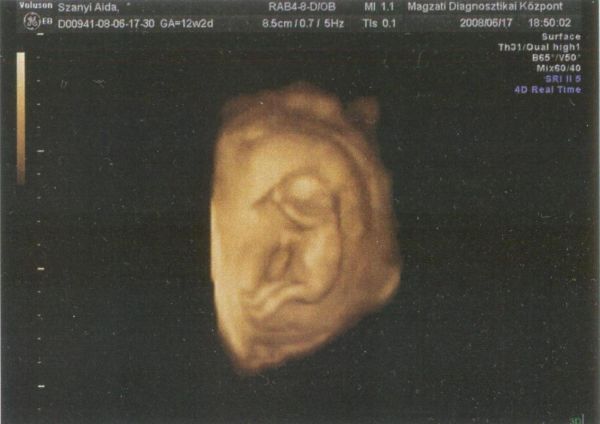

A képről: eddig úgy gondoltam, nem fogok 4D-s képet csináltatni, de teljesen felvillanyoztatok, lányok!